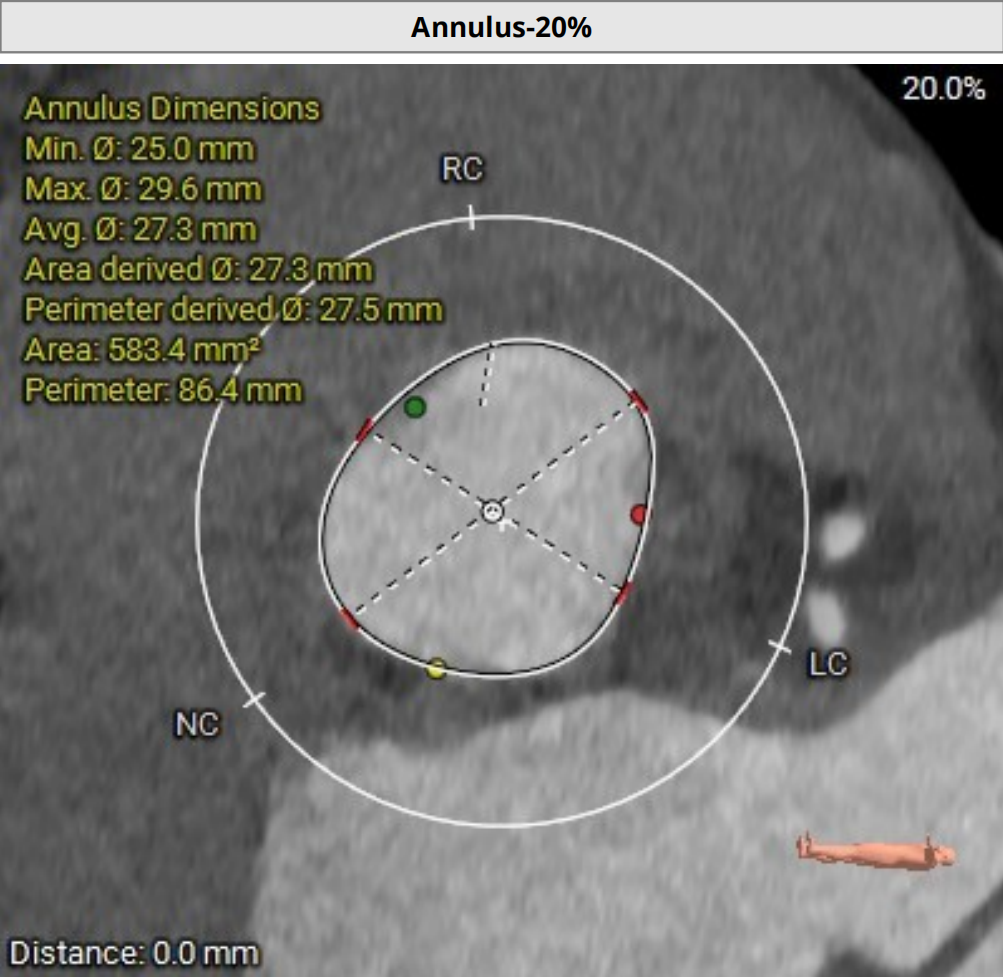

三叶式主动脉瓣,瓣叶增厚,瓣环周长76mm,选用S号TaurusTrio瓣膜。